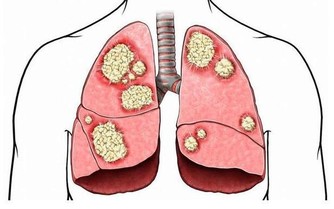

李大爺這傷口已經是典型的糖尿病足了,大家都知道一旦得了糖尿病足,潰瘍進展是很快的,而且很難癒合,所以李大爺就因為這傷口在我們科住了半個多月,還沒有痊癒,可以說是“一失足成千古恨”。